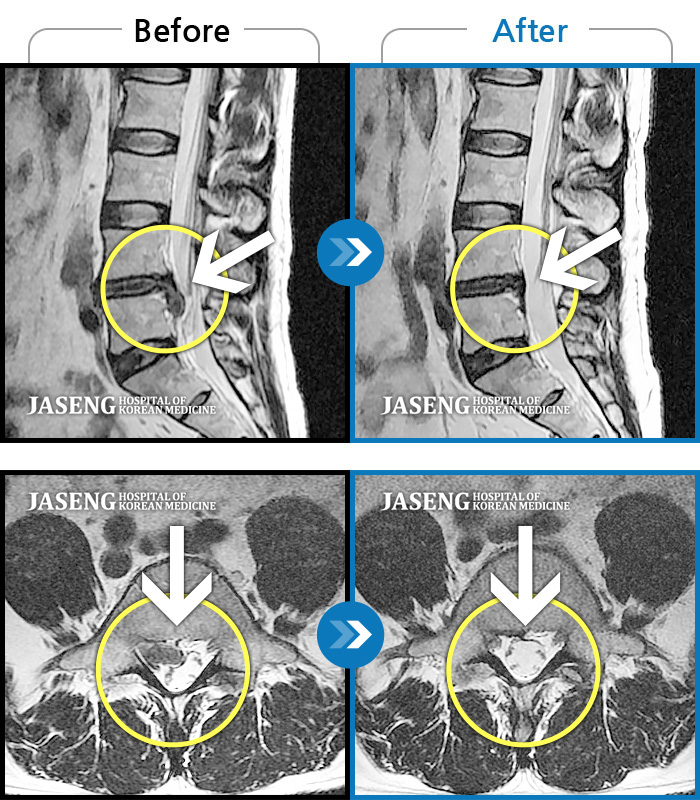

허리디스크

일산 · 김태용 원장

허리 골반통증이 극심했다.

촬영시기

2021.02.06 ~ 0222.01.15

2022.01.17